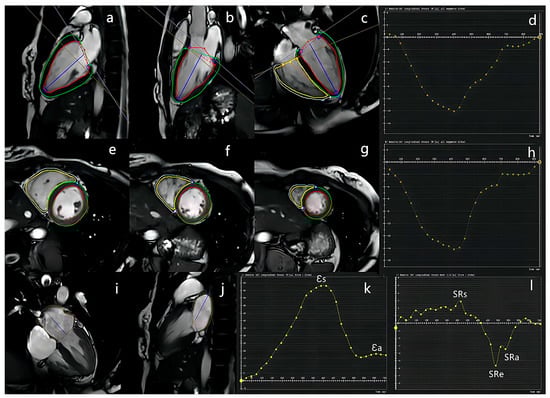

2.3.3. FT Analysis

2.4. Follow-Up